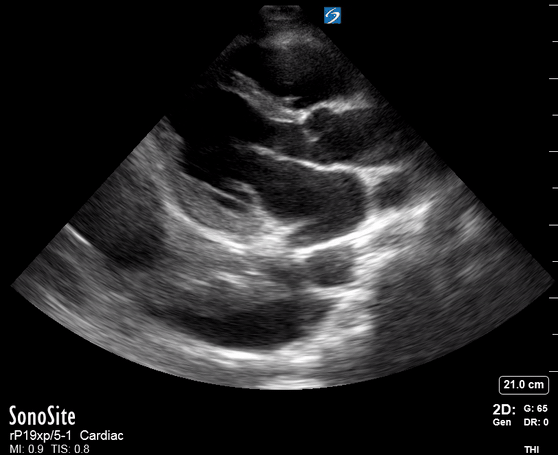

Effusion: is there a pericardial or pleural effusion?

Pericardial effusion is a continuum and can potentially evolve into haemodynamic collapse. Tamponade physiology is detectable earlier with ultrasound than with traditional physical examination, and it has been demonstrated that PoCUS improves mortality in penetrating cardiac trauma. Timely and accurate diagnosis is, therefore, vital.

THE VIEWS

The subxiphoid view is the most reliable for detecting pericardial effusion. Still, it is ideal to obtain different views not to miss a focal effusion as small amounts of fluid can lead to tamponade physiology. Tamponade does not link strictly to the size of the effusion, but correlates more with the speed of onset, causes, and haemodynamic effects.

PITFALLS & PLEURAL EFFUSIONS

A common error is to confuse a pericardial fat pad with effusion. Fatty tissue has a heterogeneous echotexture, moving in coordination with the myocardium, and it cannot be tracked around the heart, especially posteriorly and to the apex. Another pitfall is misinterpreting a pleural effusion as a pericardial effusion. However, they can be differentiated by their relationship to the descending aorta. Pericardial effusion may be seen between the aorta and the LV free wall, whereas pleural effusions are posterior to the descending aorta. Lastly, other causes, namely hypovolaemia and large pleural effusions, can cause RA and RV collapse.

CARDIAC TAMPONADE

Progressively rising pressure translates into evolving tamponade, and this accompanies a series of ultrasound findings:

Initially, the RA collapses during ventricular systole (closed AV valves).

Followed by RV collapse in ventricular diastole (open AV valves).

Ultimately leading to LV collapse.

In addition, the presence of a non-collapsible, plethoric IVC is one of the most sensitive signs of tamponade, and a finding easy to visualise. Conversely, a pericardial effusion in a haemodynamically stable patient with a collapsible IVC is unlikely to represent tamponade.